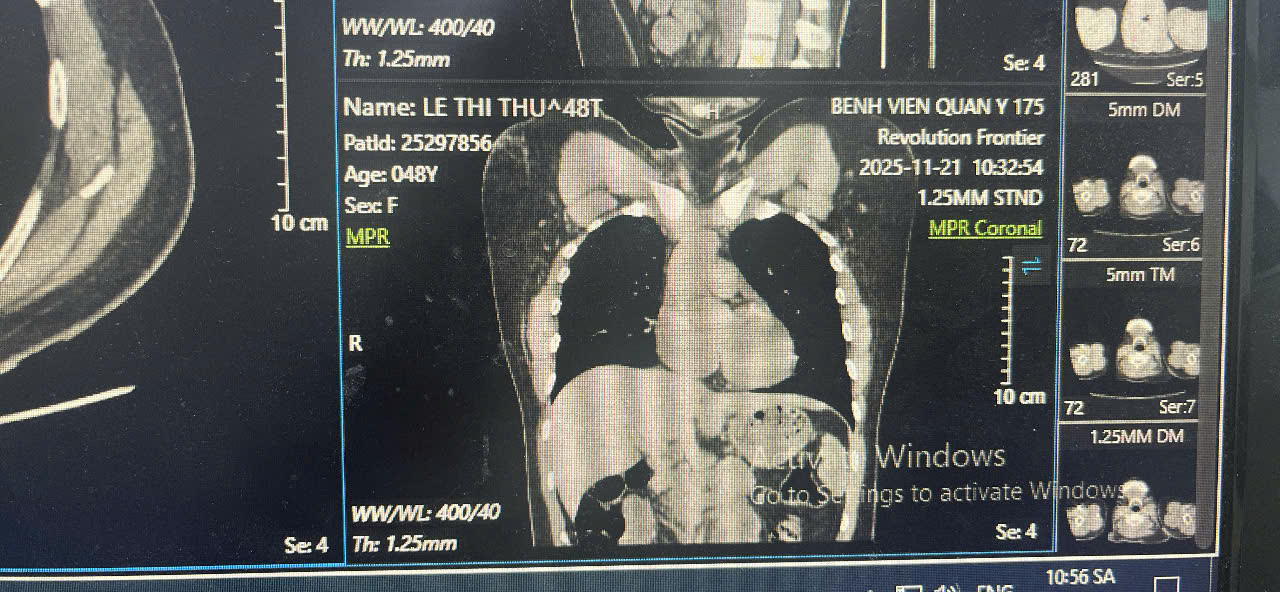

Hình ảnh CT-Scan sau khi rút dị vật

Nhờ kỹ thuật ít xâm lấn, ca can thiệp diễn ra thuận lợi, bệnh nhân tỉnh táo ngay sau thủ thuật, hồi phục tốt và xuất viện sau theo dõi ngắn.